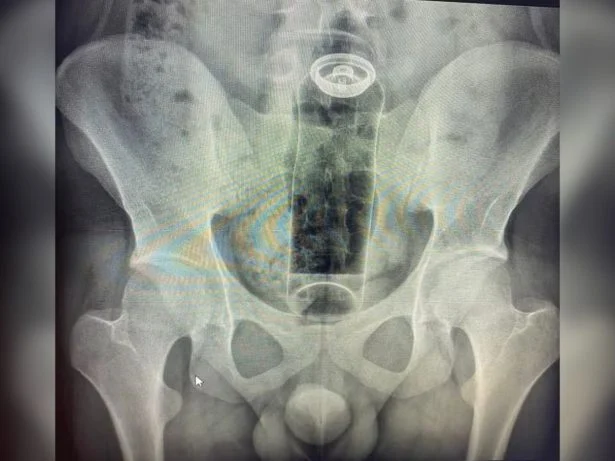

Jovem de 19 anos Internado às Pressas Após Desodorante Ficar Preso no Reto: Risco Médico Grave

Jovem de 19 anos busca ajuda médica urgente após desodorante ficar preso no reto, exigindo internação para remoção segura.

Um incidente inusitado e preocupante levou um jovem de apenas 19 anos a ser internado de urgência. O motivo: um frasco de desodorante que acabou ficando preso em seu reto, necessitando de intervenção médica imediata.

O caso, que soa como um alerta para os perigos de “brincadeiras” íntimas inadequadas, destaca a importância de buscar ajuda profissional ao lidar com situações médicas inesperadas. A impossibilidade de remover o objeto em casa forçou o jovem a procurar o hospital.

A situação ressalta os riscos associados à introdução de corpos estranhos no reto, que podem ter consequências graves para a saúde. Conforme as informações divulgadas, o procedimento de retirada foi indispensável para evitar complicações sérias.

A internação do jovem foi crucial para garantir a retirada segura do desodorante. Tentativas de remoção em casa, ou o uso de laxantes sem orientação médica, poderiam ter levado a complicações severas.

A permanência prolongada de um corpo estranho no reto representa um perigo iminente. Os riscos incluem perfurações no intestino, que podem levar a sangramentos e infecções generalizadas, conhecidas como peritonite.

Em casos extremos, a falta de intervenção adequada pode evoluir para quadros infecciosos graves, com potencial risco de vida para o paciente. A rápida ação médica é, portanto, fundamental para preservar a saúde e a integridade do indivíduo.